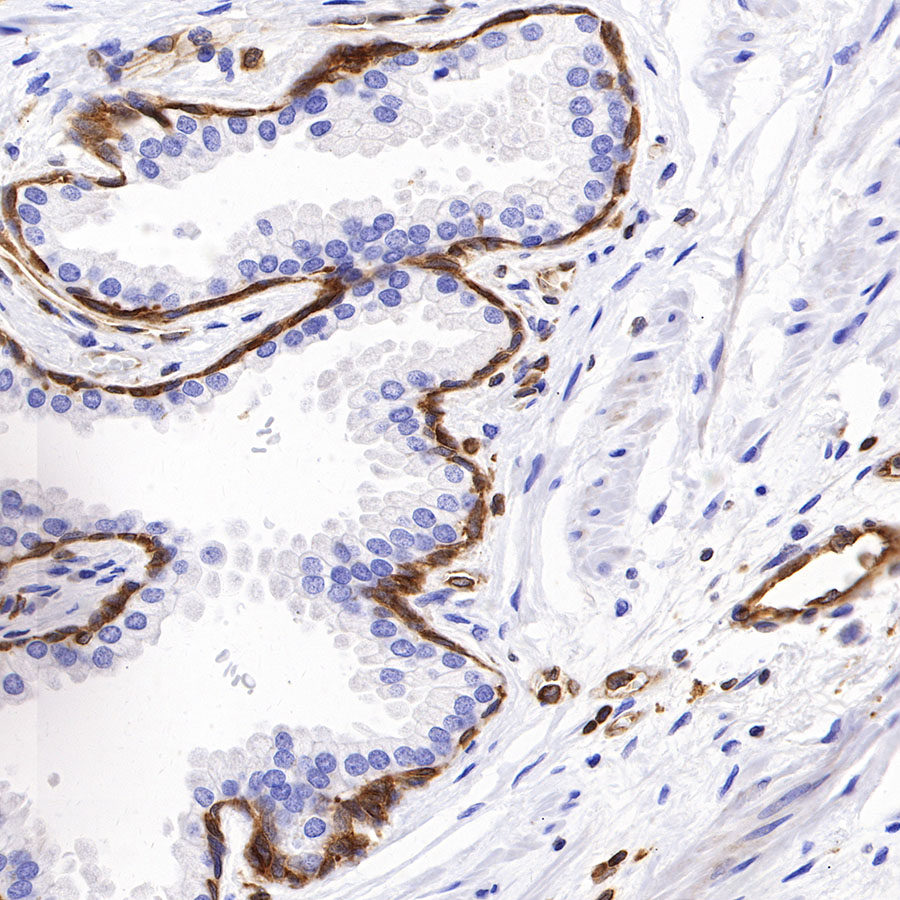

Picture

Picture

Immunohistochemistry